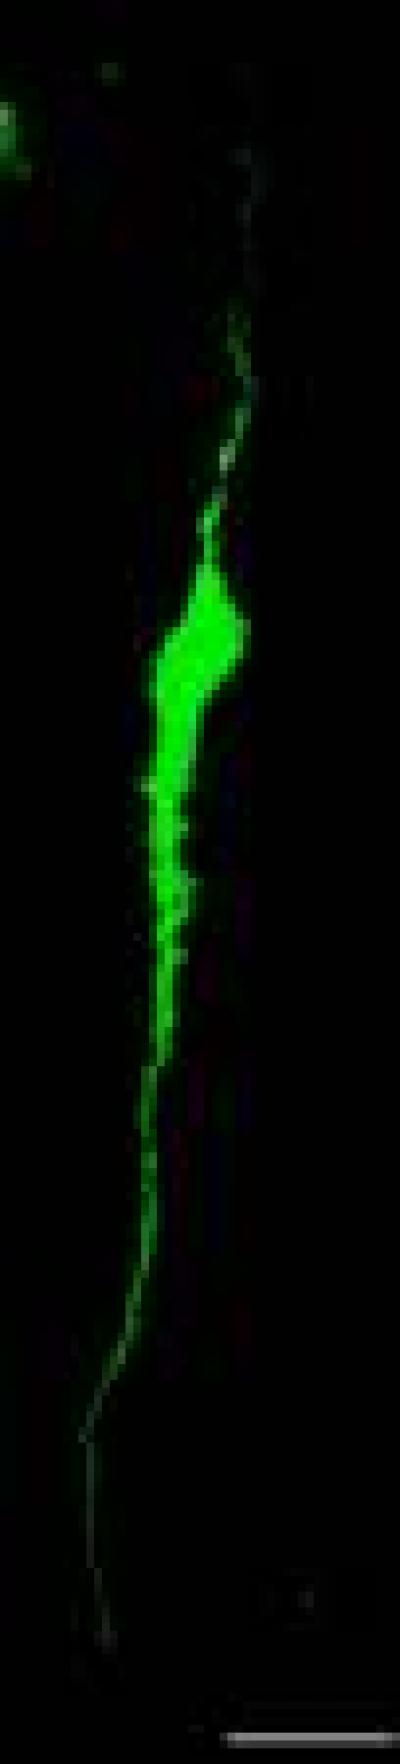

Gonadotropin-releasing hormone (GnRH) neurons in the preoptic area may undergo morphological changes during the pubertal period when their activities are upregulated. To clarify the regulatory mechanism of puberty onset, Dr. Quan Liu and co-workers from the First Hospital of Jilin University, China investigated the morphological changes of GnRH neurons in the preoptic area of GnRH-enhanced green fuorescent protein transgenic rats. Under confocal laser microscopy, pubertal GnRH neurons exhibited an inverted Y distribution pattern. Prepubertal GnRH neurons were generally unipolar and bipolar, and were distinguished as smooth type cells with few small processes or irregular type cells with many spine-like processes in the proximal dendrites. The number of GnRH neurons in the preoptic area and spine-like processes were increased during the course of reproductive maturation. There was no significant difference between male and female rats. Immunofuorescence staining revealed synaptophysin punctae close to the distal end of GnRH neurons, indicating that some presynaptic terminals may form a synaptic linkage with these neurons. The relevant study has been published in the Neural Regeneration Research (Vol. 9, No. 13, 2014).